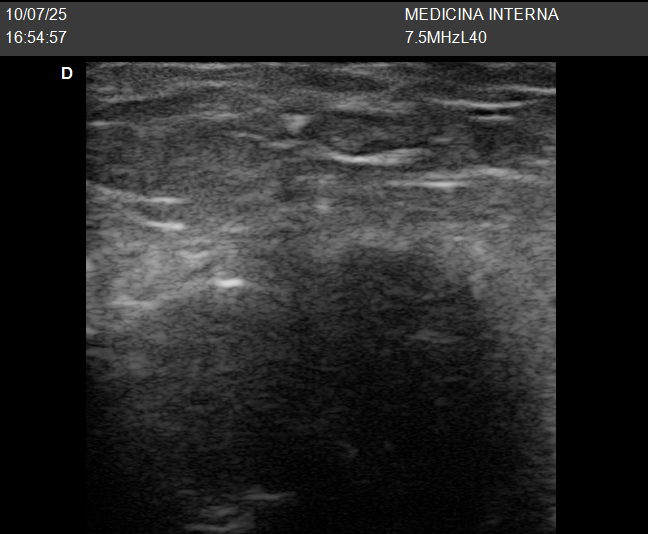

🔹 Caso 2: “Un bulto en la ingle que aparece solo al ponerse de pie”

Una mujer mayor, de más de 70 años, acude porque nota desde hace unas semanas una sensación rara en la ingle derecha, como si “algo le saliera” cuando está de pie, pero al tumbarse desaparece.

Se trataba de una hernia inguinal derecha que solo era visible en posición vertical. Esto confirma lo importante que es explorar y hacer la ecografía en la postura adecuada.